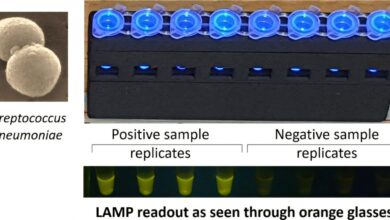

Dvacet minut bezpečného poledního slunce na předloktí a obličeji, rychlá chůze v nedalekém parku, lezení po schodech nebo surya namaskar dodat vitamín D a stimulující zátěž, která říká kostem, aby zůstaly silné. Souborová fotografie slouží pouze pro reprezentativní účely

Prevence je mnohem lepší než záchrana, a to snadno zapadá do indického způsobu života. Thali, které obsahuje dva šálky nízkotučného tvarohu nebo paneeru, hrst sezamu nebo ragi (obojí přirozeně bohaté na vápník), sklenici obohaceného tónovaného mléka a tmavě zelenou listovou zeleninu může posunout denní vápník za hranici 1 000 mg; pro ty, kteří nesnášejí laktózu, mohou pomoci sojové nebo mandlové nápoje obohacené vápníkem. Dvacet minut bezpečného poledního slunce na předloktí a obličeji, rychlá chůze v nedalekém parku, lezení po schodech nebo surya namaskar dodat vitamín D a stimulující zátěž, která říká kostem, aby zůstaly silné. Pomáhají i tradiční zvyky: tlučení koření v hmoždíři, dřep při krájení zeleniny nebo sezení se zkříženýma nohama na podlaze udrží kyčle a páteř zatížené tak, jak to moderní pohovky nedělají. Přidejte 30 minut pránájáma nebo jógu třikrát týdně, abyste zdokonalili rovnováhu, snížili riziko pádu a posílili svaly středu těla a zároveň omezili tabák a paan masala a denní alkohol na minimum. Rodiče, kteří posílají děti ven hrát kriket nebo kho-kho a nahrazují kolu podmáslím, nastaví nejvyšší možný vrchol kostní hmoty ještě před dospělostí a doslova ukládají vápník do šedesáti let svého dítěte.